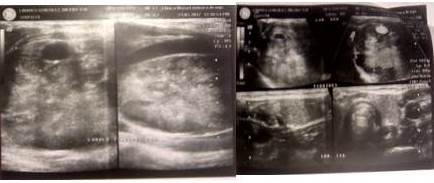

Diagnóstico por imagen, se le realiza RX de tórax, que reporta dentro de límites normales y ecosonograma de tiroides (Figura 2).

Diagnóstico de ingreso: bocio